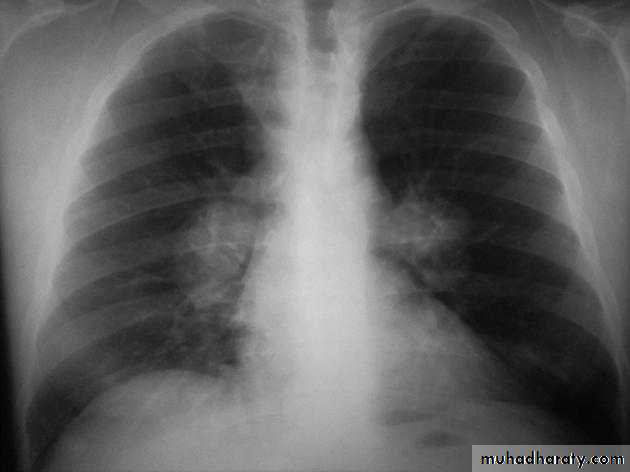

• Pleural effusion : collection of fluid within the pleural space. This can be further divided into Transudate , exudate, according to protein content .Other type of fluid collection within pleural space are

• Chest x-rays are the most commonly used examination to assess for presence of a pleural effusion, however it should be noted that on a routine erect frontal chest x-ray as much as 200-500 ml of fluid is

• required before it becomes evident .

blunting of the costophrenic angle

blunting of the cardiophrenic angle

fluid within the horizontal or oblique fissures

eventually a meniscus will be seen, on frontal films seen laterally and gently sloping medially

with large volume effusions, mediastinal shift occurs away from the effusion

• Lateral films are able to identify a smaller amount of fluid ( about75%)as the costophrenic angles are deepest posteriorly posteriorly

Pleura effusion signs

Obliteration of costo-pherinic anglesMeniscus sign

Lenticular sign